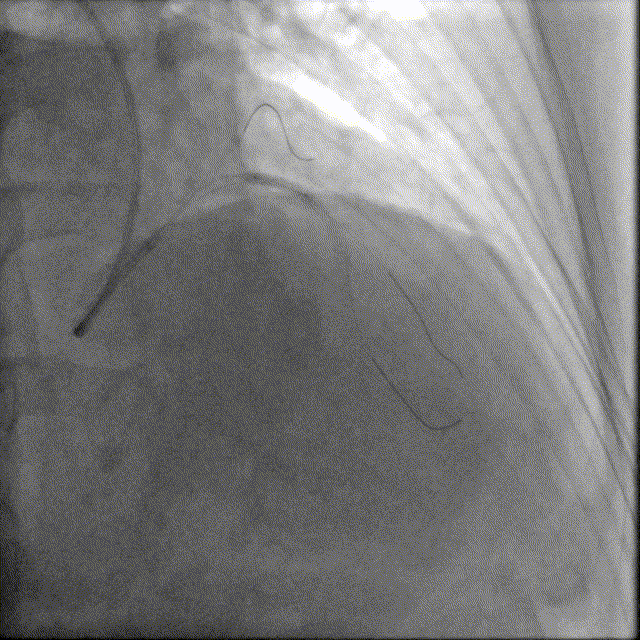

造影如下

患者左主干前三叉1,0,1型病变,主干末端偏心40%狭窄;前降支病变自开口延续至中段,口部80%狭窄,中段80%狭窄,病变位置钙化严重;回旋支近段约30%轻度狭窄,第一及第二钝缘支开口80%局限病变。